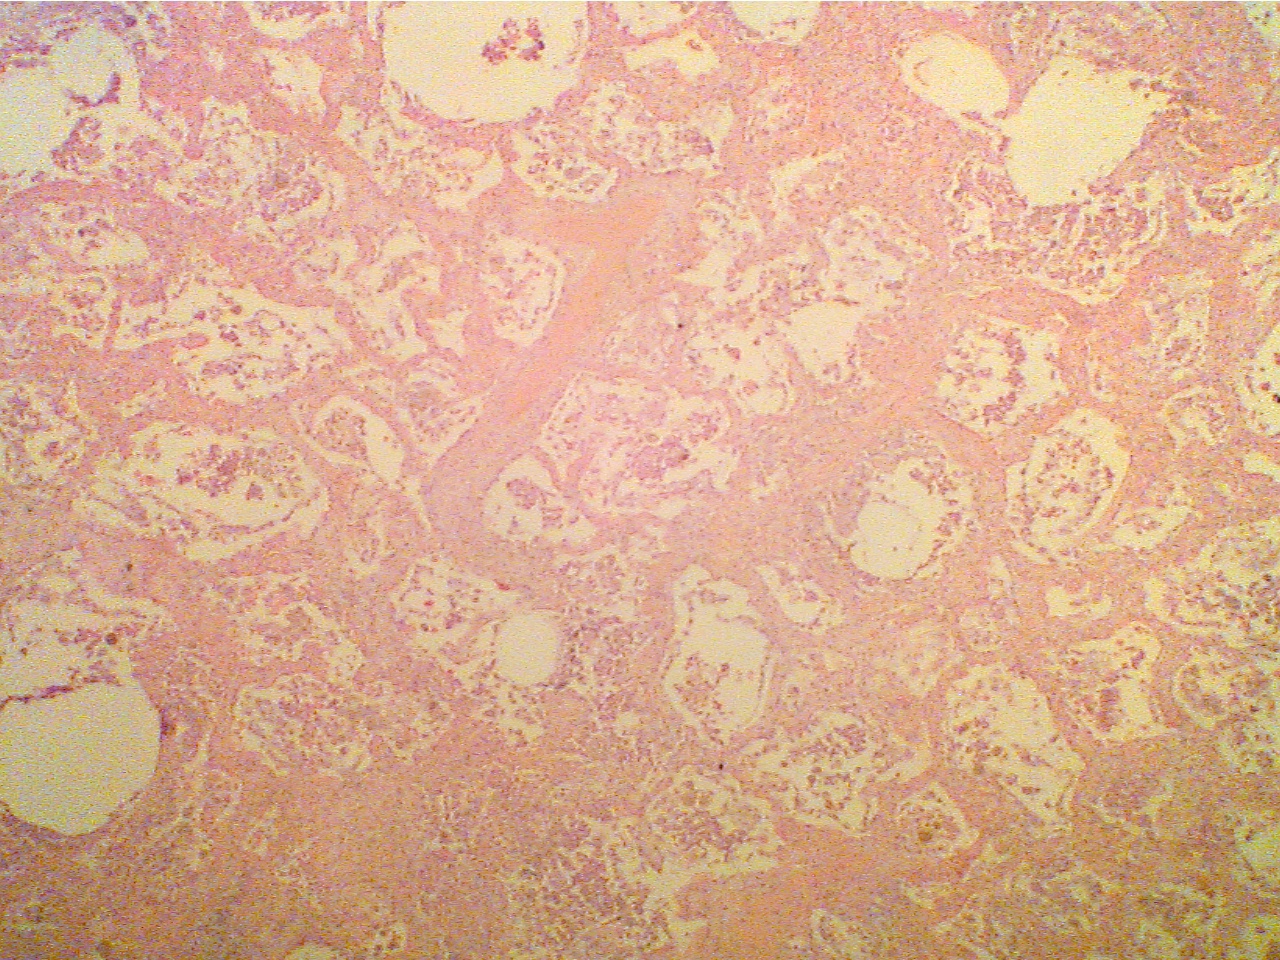

Chronic pneumonia

Compare the alveoli (air spaces) of this lung with the normal. Notice that they are filled with cells and fluid.

Pneumonia (40X2.0)                                                                         Normal lung (40X2.0)